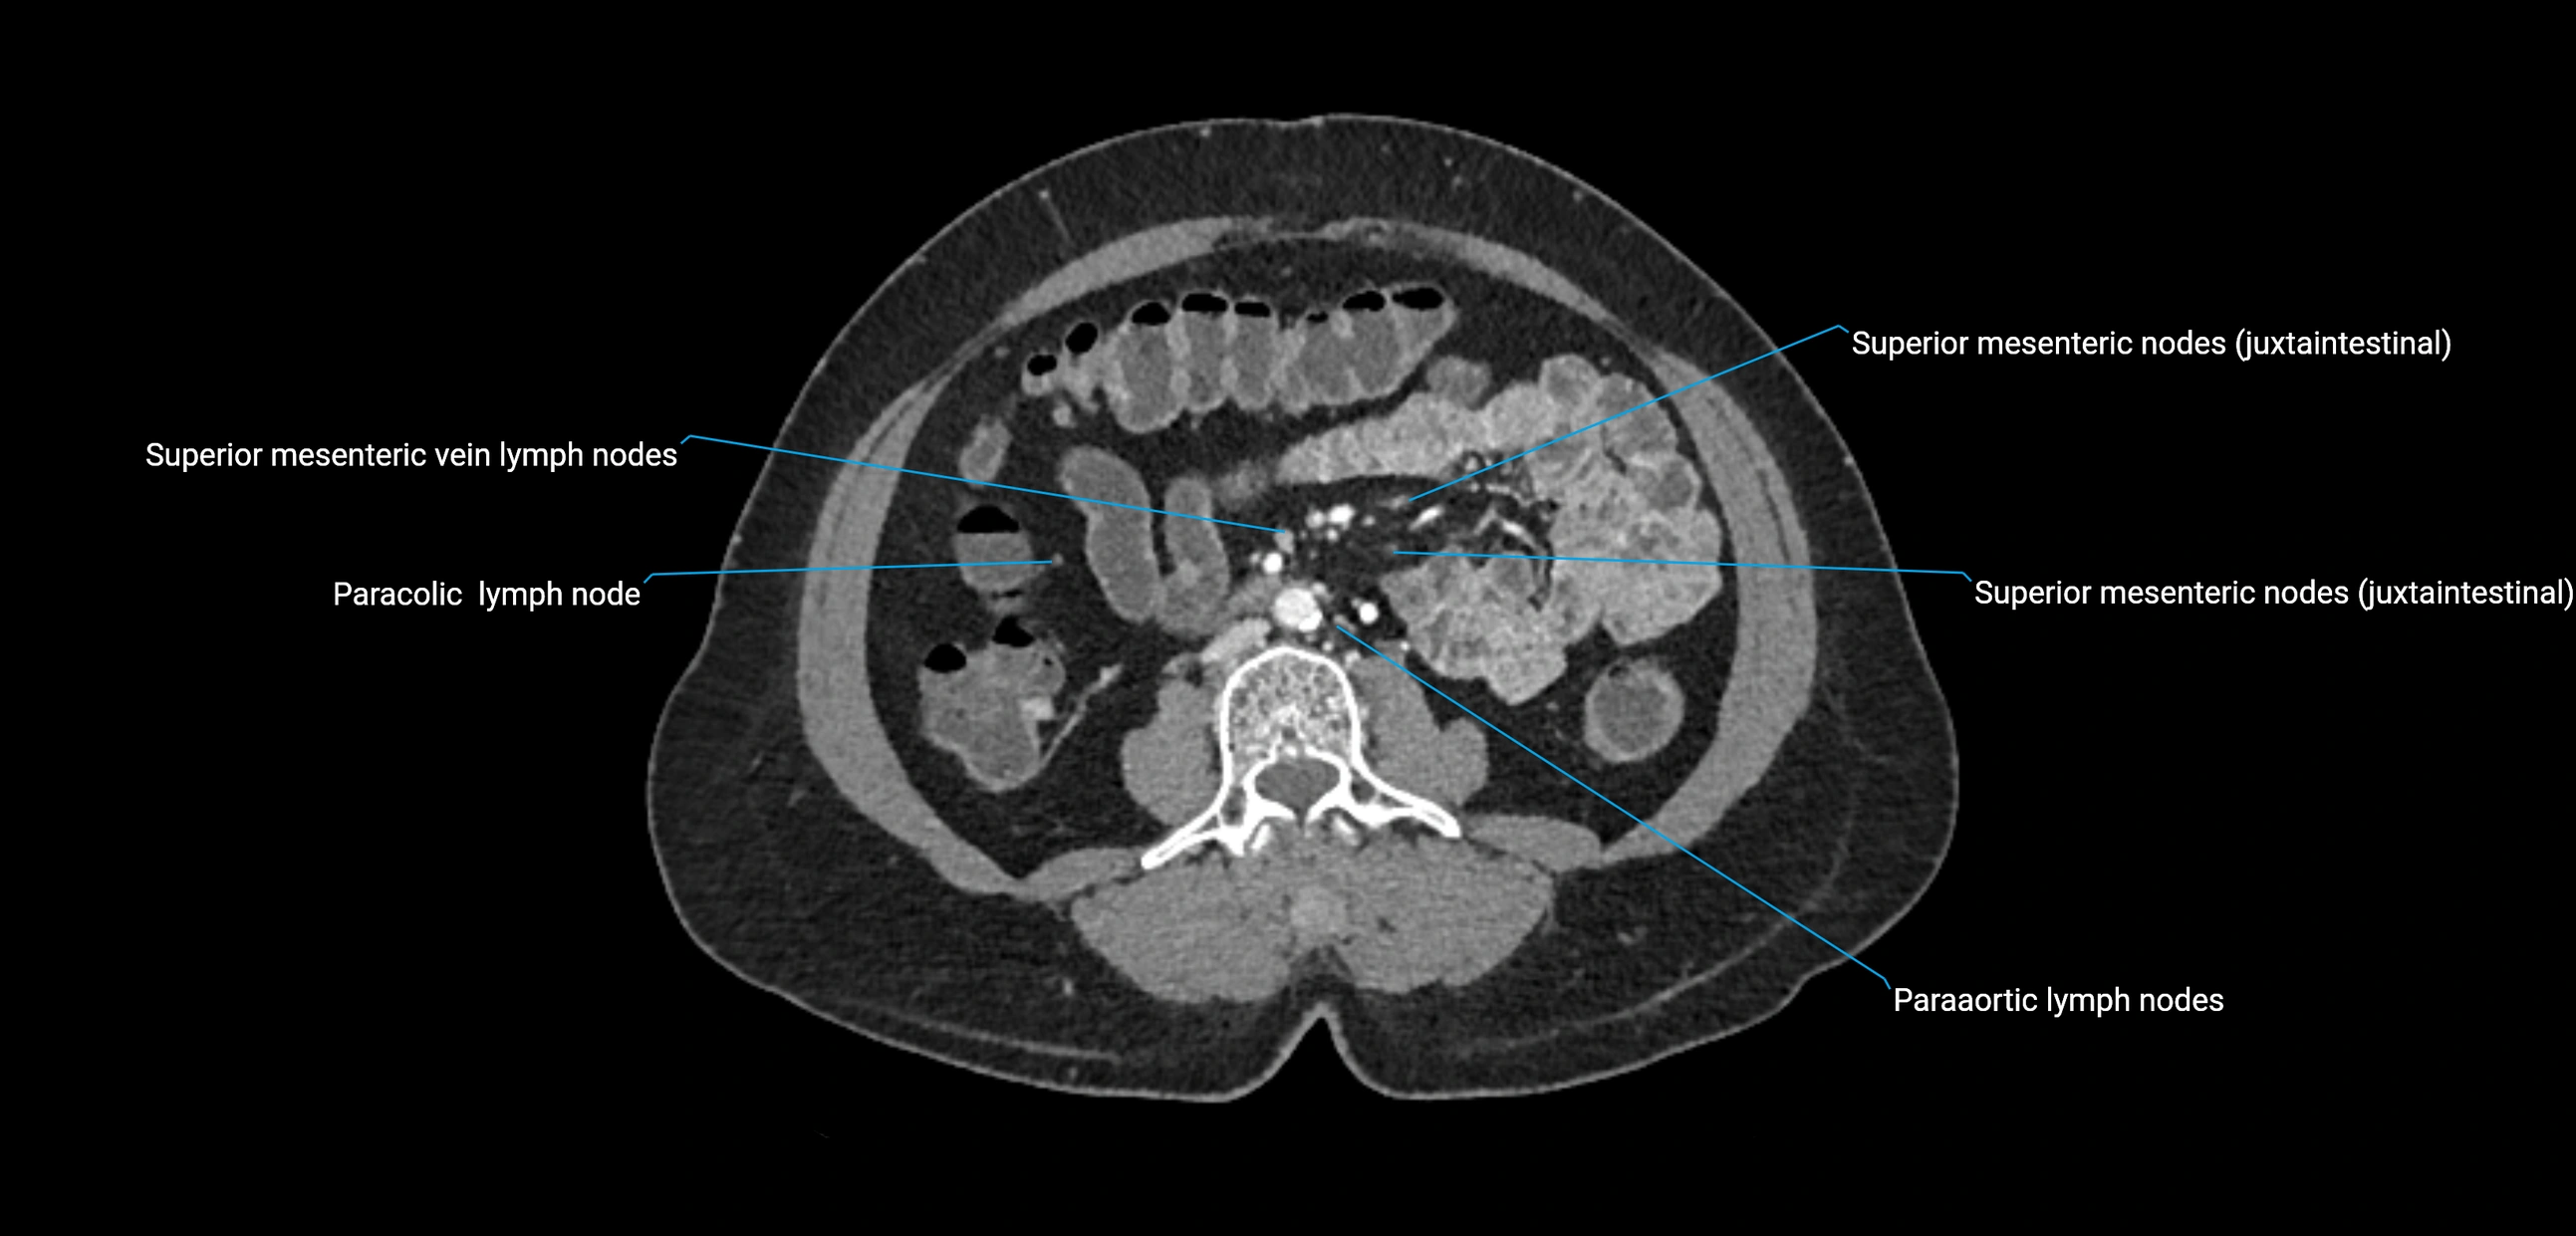

CT Appearance

CT Pre-Contrast:

• Nodes appear as soft-tissue density nodules adjacent to the aorta and IVC

• Calcification may be seen in chronic infections (e.g., tuberculosis)

CT Post-Contrast:

• Normal nodes enhance homogeneously

• Malignant nodes may show heterogeneous enhancement, central necrosis, or conglomerate formation

• Size >1 cm short axis is suspicious, though morphology and distribution are equally important